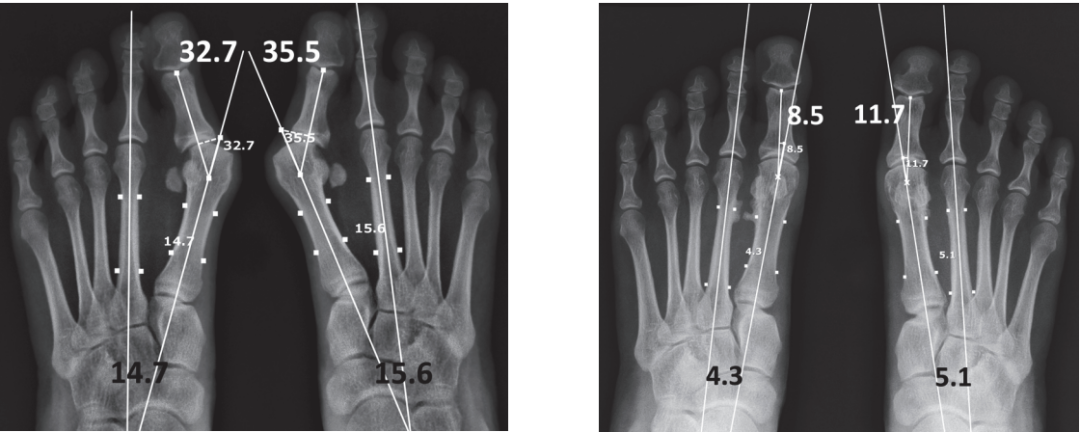

▲图示(A)47 岁女性中重度拇外翻畸形的影像学片,该患者双足均存在跖趾关节不匹配及跖籽韧带完全分离。(B)术后 2 年随访影像学片。第一跖骨复位效果良好;未松解拇收肌腱,仅分别对跖趾关节韧带、跖籽韧带进行松解,拇趾与籽骨也均实现良好复位。

▲图示(A)59 岁女性重度拇外翻的影像学片,该患者自青少年时期起即患有双侧拇外翻畸形,且因工作原因穿高跟鞋的年限超 20 年,其主要症状为跖骨痛。(B)术后 3 年随访的影像学片。尽管第一跖骨与籽骨的对位关系维持良好,但患足仍残留中度拇外翻畸形;不过该患者恢复了跑步能力,且可再次穿高跟鞋,同时跖部胼胝消失、跖骨痛症状缓解,对此效果表示满意。